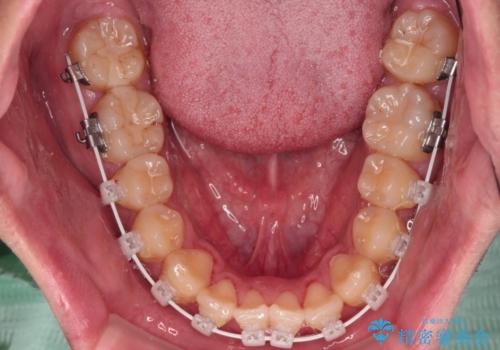

クロスバイトはありましたが、叢生の程度としては酷くなかったため、ワイヤー矯正でもマウスピース矯正でも、好きな方を選択していただきました。

一日中マウスピースを装着する煩わしさから、マウスピース矯正を継続する自信がないとのことで、ワイヤー装置にて矯正治療を行うこととしました。

気になっていたクロスバイトは速やかに改善され、1年間で治療を終えることができました。

治療開始前は汚れが多く、全体的に歯肉が腫れていましたが、矯正治療を通して腫れも少しずつ改善されました。